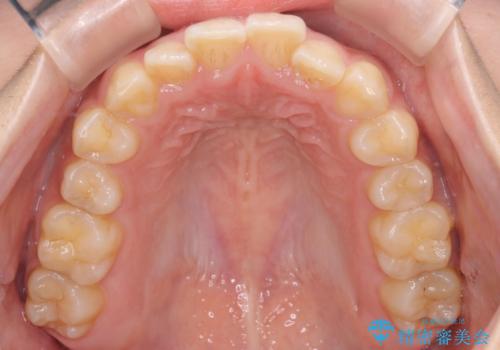

- 前歯の叢生を主訴に来院されました。非抜歯でインビザラインで治療をしました。

叢生はIPRをし、並べました。この患者様はオープンバイトだったため歯を並べる過程でかみ合わせも治しました。